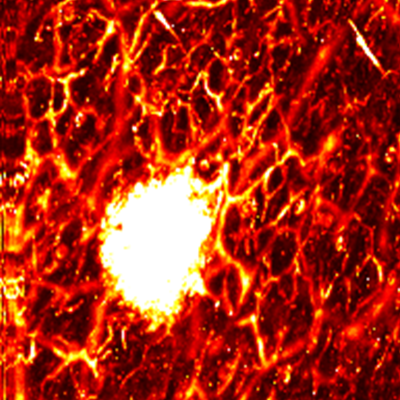

MAP